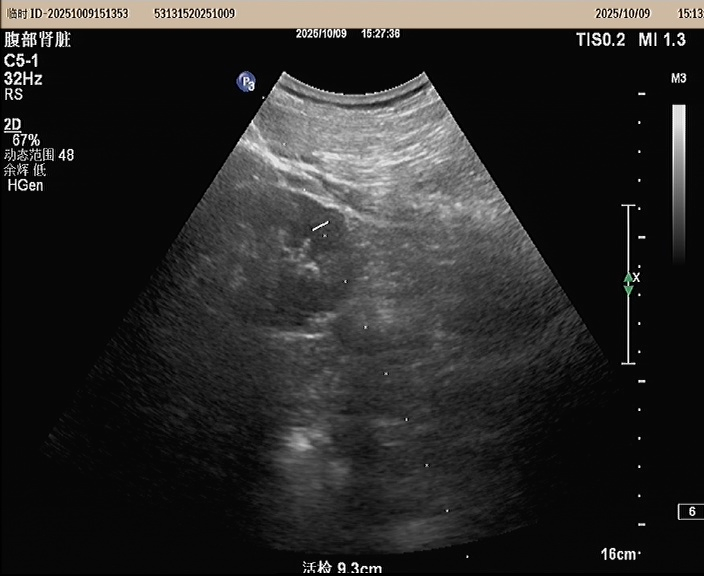

入院经过常规相关检查后考虑肾病综合征,为了进一步明确诊断,2025年10月9日,我院功能科在超声引导下行右肾下极实质穿刺活检术,病理活检:Ⅱ期膜性肾病。经治疗后患者血压控良好,下肢水肿消退,未诉特殊不适办理出院。